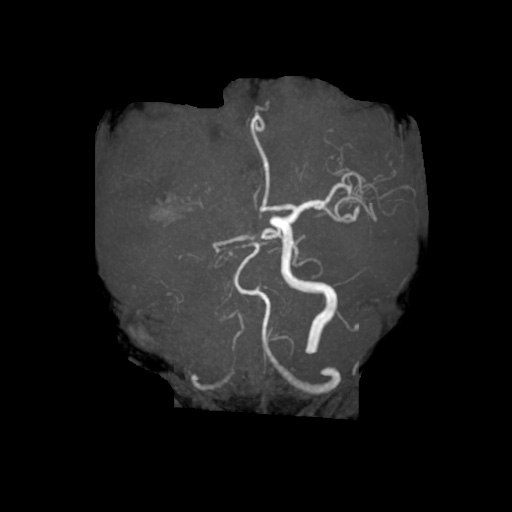

MRA検査

MRIの撮影技術を使って、血管を描出する方法です。頭蓋内外の重要な動脈(総頸動脈、内頸動脈、ウィリス輪、椎骨動脈、脳底動脈)の変化をとらえることができます。

MRIではCT検査と同様、腫瘍の大きさや形、数などがわかります。また、MRAでは脳動脈瘤、脳梗塞、脳動静脈奇形、もやもや病、閉塞性動脈病変などの脳血管障害がわかります。脳ドックでは、くも膜下出血の原因となる脳動脈瘤のスクリーニング検査としてよく用いられています。